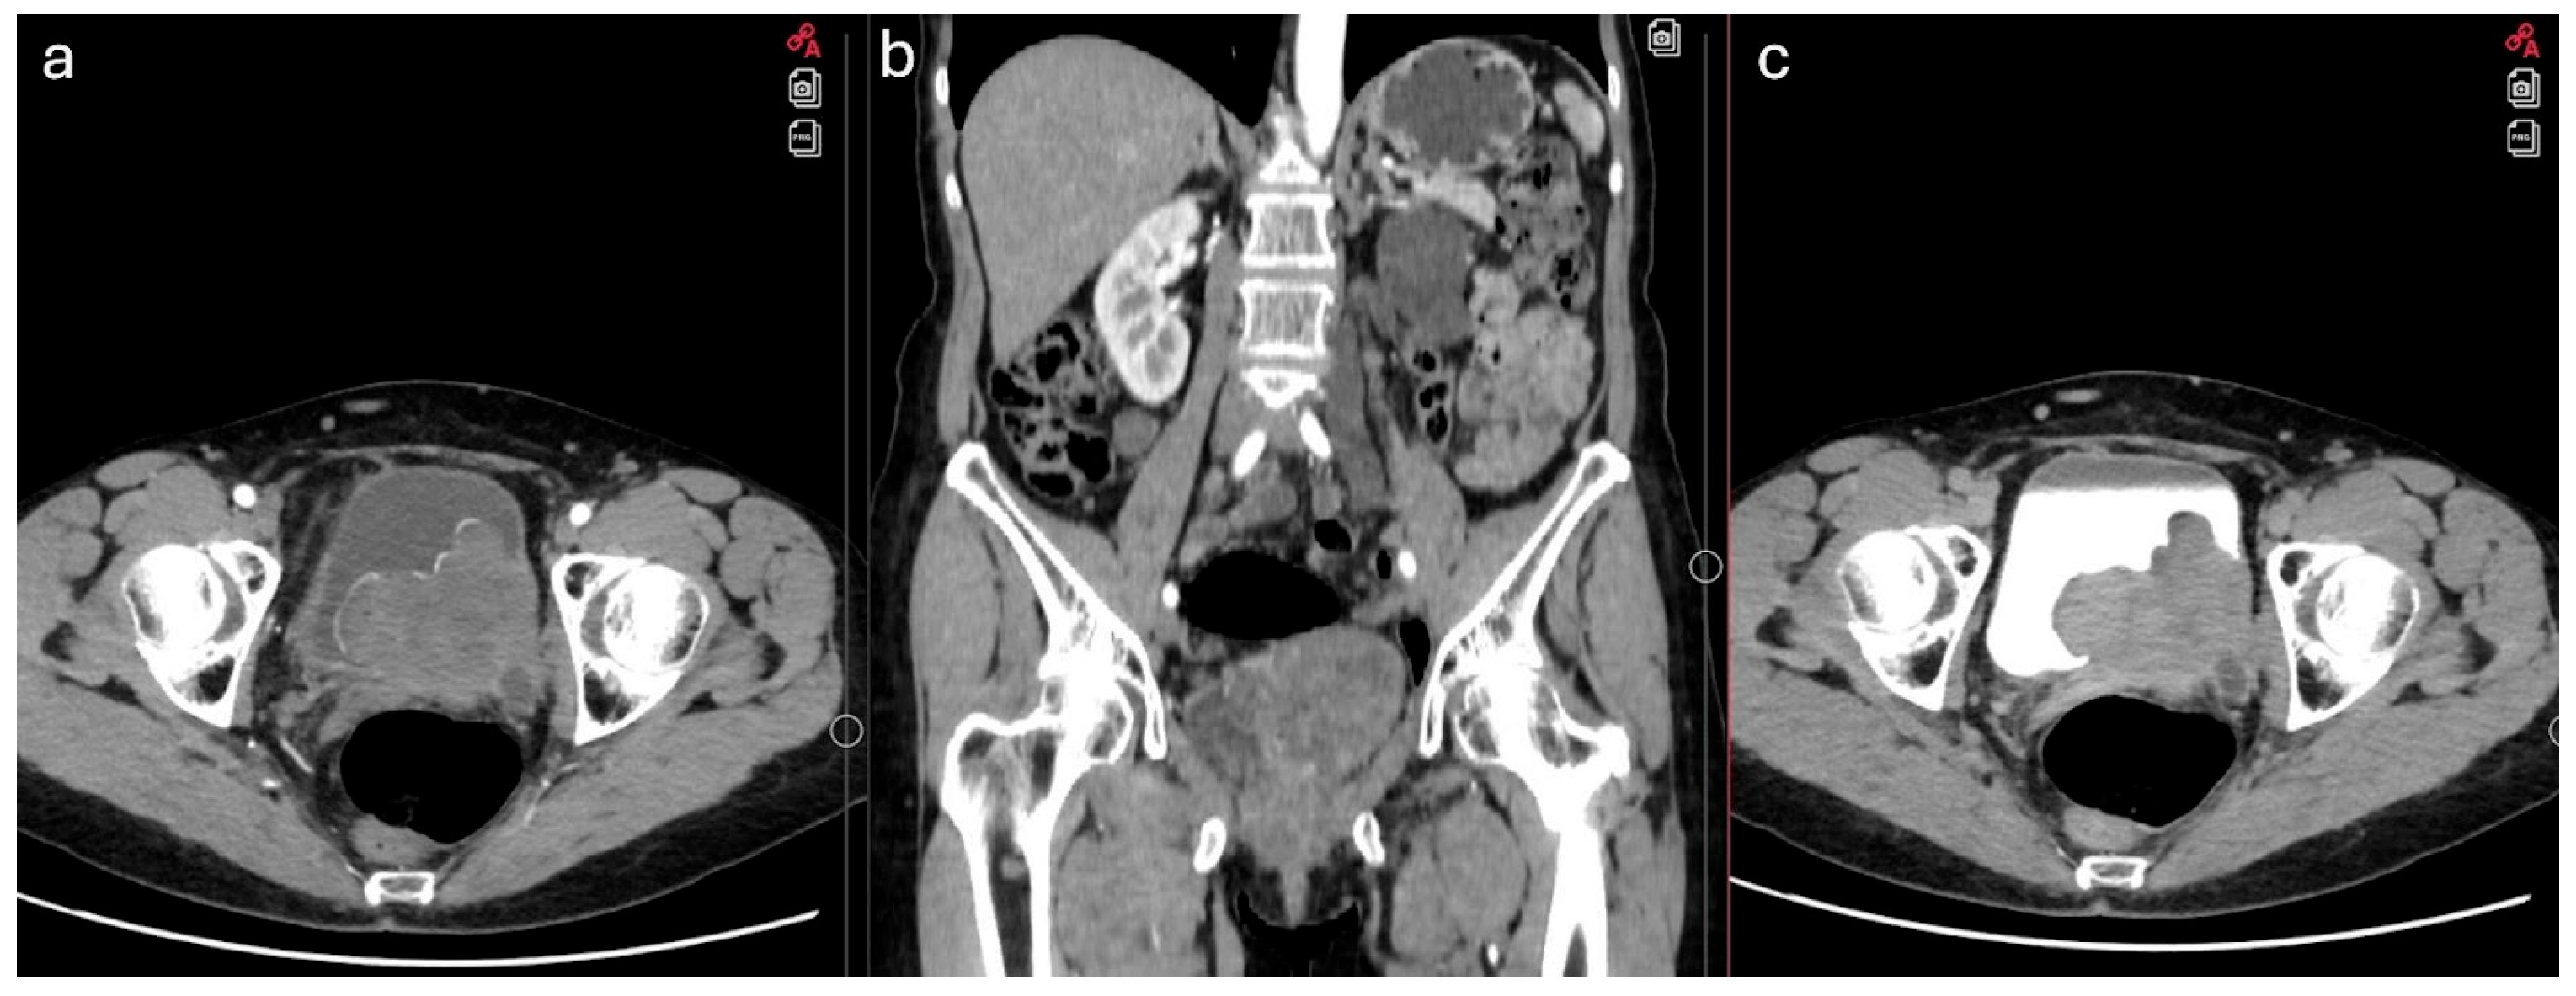

2. Case Report